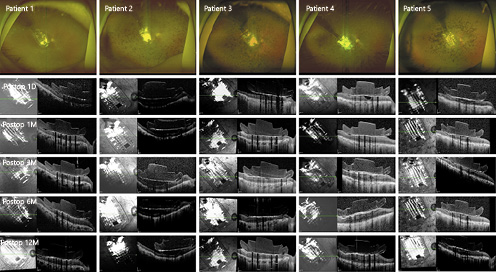

In all of the eyes, the microelectrode array was well positioned over the macula. We did not observe optic disc-to-array overlap in any eye at any postoperative visit (Fig. 1).

Postoperative fundus photographs and OCT images of the patients. In all of the eyes, the microelectrode array was well positioned over the macula. OCT revealed the development of fibrosis-like hyperreflective tissues at the interface between the array and the retina in 3 eyes (first seen in patient 1 at 12 postoperative months and in patients 3 and 4 at 3 postoperative months).

Postoperative fundus photographs and OCT images of the patients. In all of the eyes, the microelectrode array was well positioned over the macula. OCT revealed the development of fibrosis-like hyperreflective tissues at the interface between the array and the retina in 3 eyes (first seen in patient 1 at 12 postoperative months and in patients 3 and 4 at 3 postoperative months).

Mean Electrode-to-Retina Distance

Postoperatively, the array was completely apposed to the retinal surface in 4 patients and remained in good contact with the underlying macula for 12 postoperative months. The mean distance of between the bottom of the implant and the top of the retinal surface for 898 out of 1,000 electrodes of 4 patients (patients 1, 3, 4, and 5) was 9.2 µm (range 0.0–131.5). In patient 2, who had a preexisting macular concavity, the mean distance at 1 postoperative month (288.8 µm) remained stable over 12 postoperative months (282.1 µm; Fig. 1, 2a).

a Postoperative gap between the electrode and the retina. Patient 2, who had a preexisting macular concavity, showed a considerable mean gap, which remained stable over 12 months. The array was completely apposed to the retinal surface in the other 4 patients. b Thickness of the fibrosis at the midline. c Retinal thickness at baseline, and postoperative periods. After retinal fibrosis-like hyperreflective tissues developed, the retinal thickness tended to increase over time.

a Postoperative gap between the electrode and the retina. Patient 2, who had a preexisting macular concavity, showed a considerable mean gap, which remained stable over 12 months. The array was completely apposed to the retinal surface in the other 4 patients. b Thickness of the fibrosis at the midline. c Retinal thickness at baseline, and postoperative periods. After retinal fibrosis-like hyperreflective tissues developed, the retinal thickness tended to increase over time.

Retinal Morphologic Changes

OCT revealed the development of fibrosis-like hyperreflective tissues at the interface between the array and retina in 3 eyes, with an onset period ranging from 3 to 12 months after implantation (Fig. 1, 2b; Table 2). After the occurrence of retinal fibrosis-like tissues, the retinal thickness tended to increase over time (Fig. 2c).